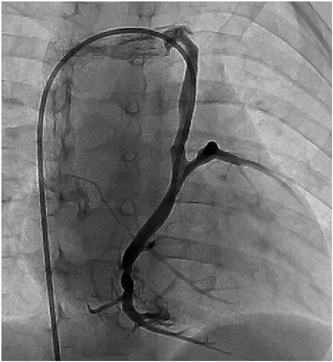

A 12 month-old male infant with known tricuspid and pulmonary atresia was admitted to our hospital for cardiac catheterization to evaluate his hemodynamic status prior to undergoing a bidirectional Glenn shunt (BDG) procedure. He was known to have undergone a left modified Blalock-Taussig shunt at 1 month of age, as well as an enlargement of an atrial septal defect using cardiopulmonary bypass at 4 months of age, and it was at this time that a coronary sinus orifice was intraoperatively identified. He had presented with dyspnea on exertion and cyanosis with systemic oxygen saturation of 85%. A chest X-ray showed a cardiothoracic ratio of 60% and a marginal decrease in the left pulmonary blood flow. Echocardiography showed that a left ventricular ejection fraction was 68% without significant valvular regurgitation. Electrocardiography showed the left axis deviation, right atrial hypertrophy and left ventricular hypertrophy without any ischemic change. Suprasternal echocardiography did not show any abnormal blood flow draining into the INV. Cardiac catheterization revealed that the pulmonary to systemic blood flow ratio, the mean pulmonary arterial pressure, the pulmonary arterial index, and cardiac index were 0.83, 9 mmHg, 154 cm2/m2, and 4.69 L/min/m2, respectively. However, a late phase left ventriculography image following angiographic evaluation of LSVC which was performed to investigate a veno-venous collateral showed retrograde blood flow through LSVC. Therefore, a 5Fr-left Judkins catheter was introduced from the femoral vein and advanced through the INV and the persistent LSVC into the coronary vein. A selective coronary venogram revealed that the coronary sinus ostium was absent and a retrograde coronary venous flow was observed through the persistent LSVC draining into the INV, i.e. a CSOA was identified (Fig. 1, Movie). When he was 19 months of age, we performed a BDG, repair of the coronary sinus orifice, and ligation of the LSVC. A re-median sternotomy was performed and after establishing cardiopulmonary bypass with bicaval cannulation, the left Blalock-Taussig shunt was ligated and divided. Following cardiac arrest using cold cardioplegia and a right atriotomy was performed, and a thin membrane was observed at the orifice of the coronary sinus (Fig. 2). We cut this membrane with enlargement of the orifice to adequately view the middle cardiac vein. Subsequently, the LSVC was ligated superiorly and divided, and after the right superior vena cava was divided, a bidirectional cavopulmonary shunt was performed. The patient was successfully weaned from the cardiopulmonary bypass and recovered uneventfully. A selective coronary angiography performed at 2 weeks after the BDG procedure showed adequate coronary venous flow draining into the right atrium. The patient was treated with oral administrations of asprin, diuretics and digoxin.

Fig. 1 A selective angiogram of the coronary vein is shown. The orifice of the coronary sinus is not visualized and the blood flow from the coronary veins is drained into the innominate vein through the persistent left superior vena cava